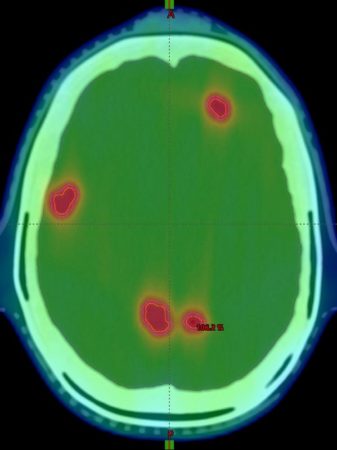

Die Schwierigkeit bei der Simultanbestrahlung: Neben der Anzahl und Größe der Metastasen führen auch die unterschiedlichen Abstände der Metastasen zueinander und zum virtuellen Bestrahlungszentrum zu technisch bedingten Unsicherheiten. „Mit unserer Forschung wollen wir diese neue Technik der Simultanbestrahlung noch sicherer und präziser machen“, sagt Studienleiter Prof. Dr. Dimos Baltas, Leiter der Abteilung für Medizinische Physik der Klinik für Strahlenheilkunde am Universitätsklinikum Freiburg.

Dafür werden die Forschenden verschiedene anatomische und technische Einflussfaktoren individuell untersuchen und bewerten. In speziellen 3D-gedruckten Schädeln, die als Pseudo-Patient*innen behandelt werden, wird die angewandte Strahlendosis mit Hilfe modernster Methoden exakt gemessen. Hier kommt insbesondere eine hochauflösende, dreidimensionale Messung der Strahlendosis zum Einsatz, welche auf speziellen Polymergelen und Magnetresonanztomografie basiert. Eine besonders hochauflösende Magnetresonanz-basierte Dosisablesung wird dafür von der Arbeitsgruppe von Prof. Dr. Michael Bock von der Klinik für Diagnostische und Interventionelle Radiologie – Abteilung Medizinphysik des Universitätsklinikums Freiburg entwickelt, die Partner im Forschungsprojekt ist.